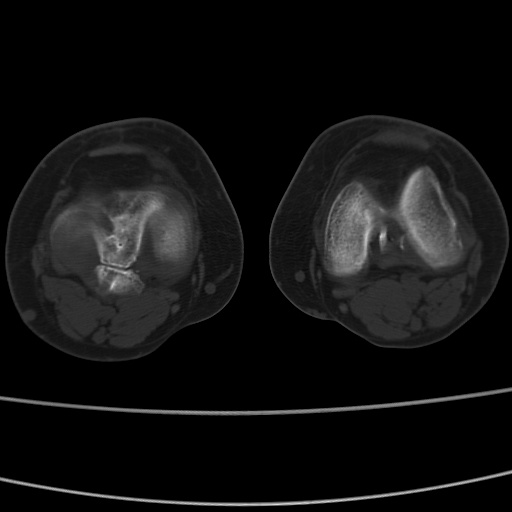

女性,50岁。【请提供患者临床症状体征】

右膝关节退行性改变,关节游离鼠。

右膝关节退行性改变,滑膜黏液囊钙/骨化并游离。